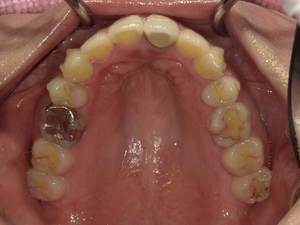

befor→after

●ご相談内容:歯の出っ張り●矯正の種類:マウスピース型矯正「インビザラインGO」●治療期間:13週間●治療費用:44万円(税込)